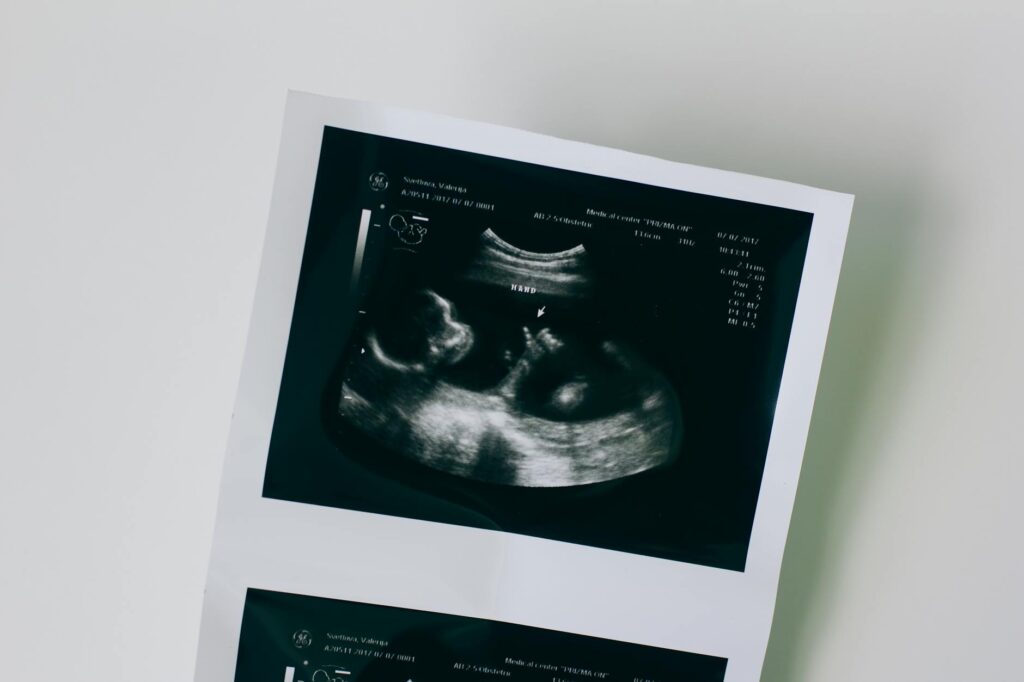

Can a father’s lifestyle choices before conception influence the health of his future children? New research 12 reveals that environmental factors affecting fathers can leave molecular footprints in embryos, shaping development and potentially impacting long-term health.

While maternal epigenetic inheritance seems intuitive given the direct biological connection between mother and developing embryo during pregnancy, emerging research demonstrates that fathers can also transmit environmentally induced epigenetic changes to their children. However, how common this phenomenon is and the mechanisms driving it have remained largely mysterious.

This comprehensive study examined how specific paternal environmental conditions affect early embryonic development in mice under carefully controlled genetic and environmental conditions. To create environmental perturbations, prospective mouse fathers were exposed to either antibiotics that disrupted their gut microbiome or a low-protein, high-sugar diet. Using in vitro fertilization to minimize experimental variability, researchers collected embryos approximately four days after fertilization and analyzed each individually to measure differences in gene expression compared to control embryos from untreated fathers.

Both environmental perturbations caused significant changes in embryonic gene expression. To understand how genetic background influences these effects, scientists repeated experiments using a different mouse strain, the equivalent to a different mouse race. The results they obtained differed, suggesting a complex interplay between genetics and environment in inheritance.

Paternal age was a factor that also resulted in changes. Embryos derived from older fathers showed stronger effects on gene expression, particularly in genes involved in immunity. This indicates that paternal age, and not only maternal one, has effects on the offspring.

The findings challenge traditional views of inheritance and suggest that a father’s preconception health and environmental exposures may have more profound effects on offspring than previously recognized. The long held view that only maternal age affected (negatively) the embryos needs to be updated to include paternal influence. Understanding how epigenetic influences (from both parents) influence embryonic development could inform clinical recommendations and contribute to personalized approaches to family planning and disease prevention. Already the finding that paternal health status –and age– influence the unborn embryo has potential to revolutionise our current understanding of the role of each parent in their offspring.